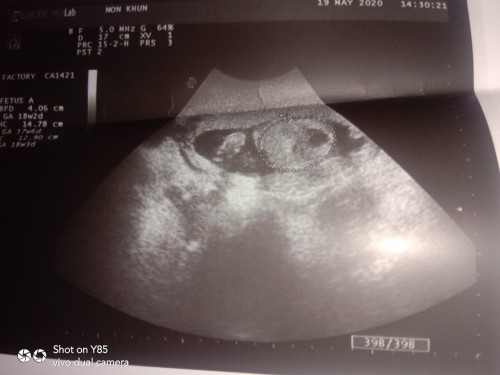

7wก็ยังใม่เจอเหมือนกันคะ หมอนัดซาวอีกรอบตอน18w ยังกังวนว่าเขาจะยังยุไหม

เคยคะท้องเเรกเราท้องลม คะเเต่ตอนนี้ท้อง2น้องได้10วีค3วันเเล้วคะ